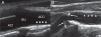

La ecografía en manos del internista permite responder preguntas clínicas concretas de forma rápida en el lugar de atención al paciente. Esta técnica «potencia» los sentidos del clínico y mejora su capacidad para resolver los problemas del enfermo. La ecografía clínica ha mostrado una buena precisión en el diagnóstico de diversas patologías cardíacas, abdominales y vasculares. También es útil para la evaluación de la patología tiroidea, osteoarticular y de partes blandas. Además, el uso de la ecografía para guiar procedimientos invasivos (accesos venosos, toracocentesis, paracentesis) reduce el riesgo de complicaciones. Presentamos 5casos para ilustrar la utilidad de esta técnica en la práctica clínica habitual del médico internista: a)miocardiopatía periparto; b)ateromatosis carotídea subclínica; c)aneurisma de aorta abdominal asintomático; d)tendinitis de los tendones largo del bíceps braquial y supraespinoso, y e)hematoma espontáneo en sóleo.

Ultrasonography in the hands of the internist can answer important clinical questions quickly at the point of patient care. This technique “enhance” the senses of the physicians and improves their ability to solve the problems of the patient. Point of care ultrasonography performed by clinicians has shown good accuracy in the diagnosis of diverse cardiac, abdominal and vascular pathologic conditions. It may also be useful for evaluation of thyroid, osteoarticular and soft tissue diseases. Furthermore, the use of ultrasound to guide invasive procedures (placement of venous catheters, thoracentesis, paracentesis) reduces the risk of complications. We present 5cases to illustrate the usefulness of this technique in clinical practice: (i)peripartum cardiomyopathy; (ii)subclinical carotid artery atherosclerosis; (iii)asymptomatic abdominal aortic aneurysm; (iv)tendinitis of long head of biceps brachii and supraspinatus, and (v)spontaneous soleus muscle haematoma.